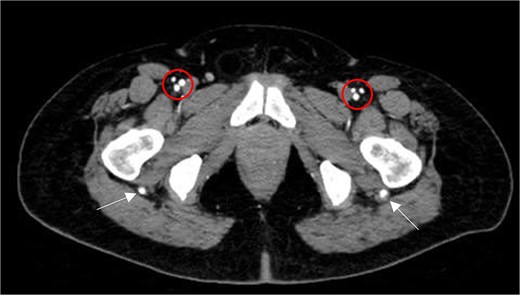

Subsequently, the patient underwent computed tomography angiography (CTA) of the lower extremities which revealed bilateral PSA (Fig. 1). The common femoral arteries trifurcated normally (Fig. 2), but the left superficial femoral artery (SFA) was significantly narrowed (Fig. 3). At the level of the knee, the right SFA joined the PSA to form the popliteal artery (Fig. 4). On the left side, the hypoplastic SFA converged with the PSA more proximally (Fig. 4); however, the artery was occluded, with no clear continuation into the popliteal artery (Fig. 4). Nevertheless, a markedly sub-occluded left popliteal artery was noted at the level of the fibular head, giving rise to a hypoplastic anterior tibial artery and tibio-peroneal trunk (Fig. 4). These findings align with Ahn-Min’s type I bilateral PSA (Fig. 5).

Axial CTA image shows normal femoral trifurcation (circles) and prominence of bilateral PSAs (arrows).